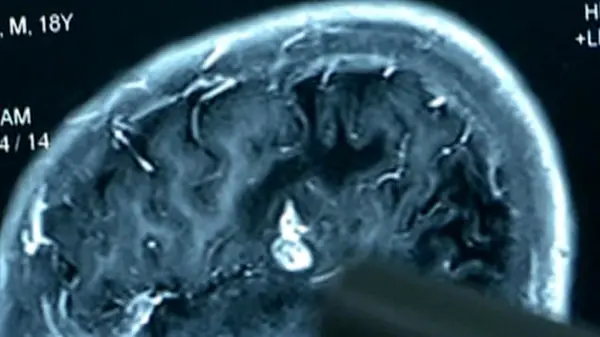

به گزارش گروه ترجمه رکنا، جراحان بیمارستانی در چین طی یک جراحی سخت و طولانی توانستند کرمی 12.7 سانتی متری را از مغز بیمار خارج کنند.

این مرد23 ساله به پزشکان گفت که از سن 6 سالگی از ناحیه دست و پا احساس کرختی می‌کرد اخیرا به دلیل بی حسی در قسمت بالاتنه خود در بیمارستان بستری شده بود وپزشکان پس از انجام آزمایش سی تی اسکن این انگل را در مغز این جوان مشاهده کردند.